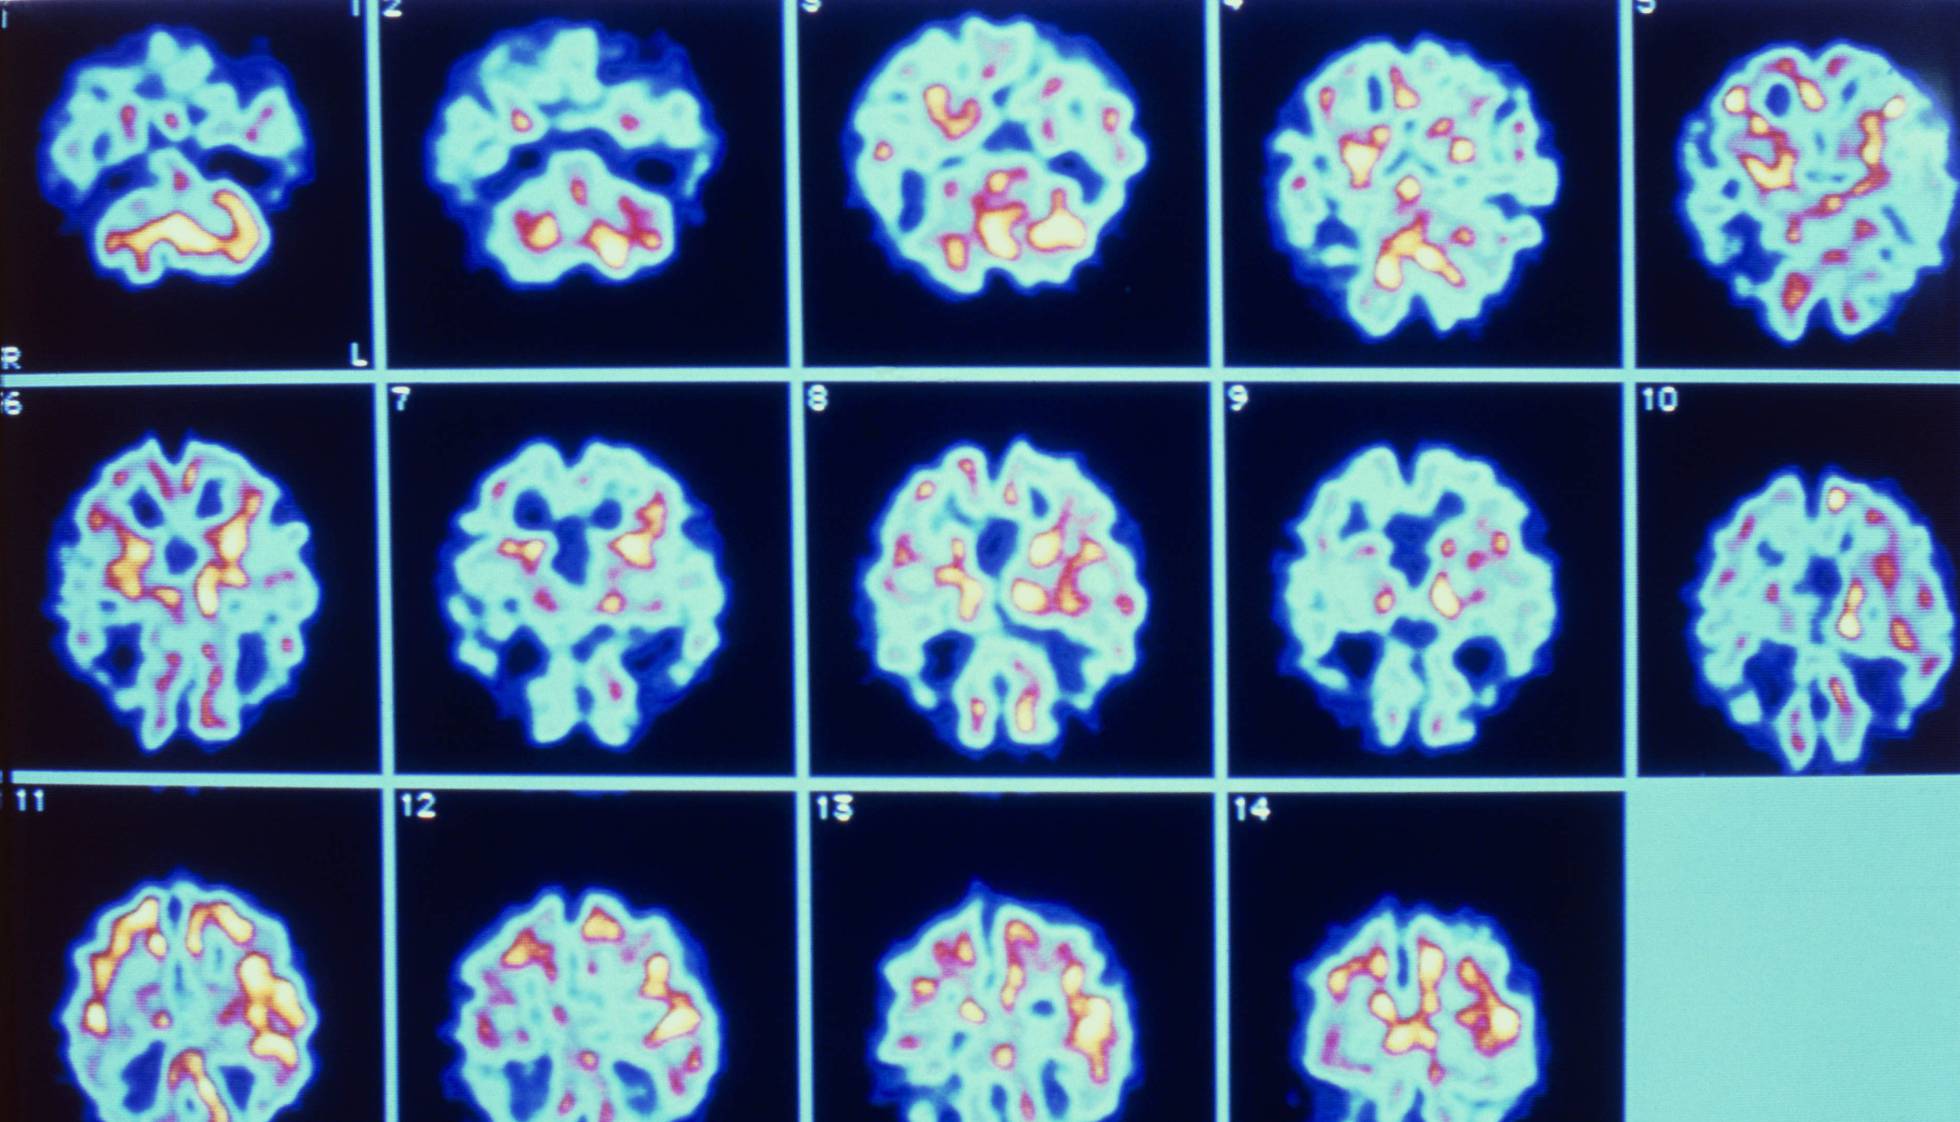

Alzheimer, a causa mais frequente de demência, é um dos grandes desafios de saúde dos países desenvolvidos. Aproximadamente 50 milhões de pessoas padecem essa doença em todo o mundo. As previsões são claras: o envelhecimento progressivo das populações e o aumento na expectativa de vida farão com que esse número duplique em 20 anos.

Infelizmente, a pesquisa do Alzheimer está particularmente recheada de obstáculos, incógnitas e frustrações. Para começar, não sabemos ainda o que provoca a doença. Sabemos que a genética e os fatores ambientais têm seu papel, mas isso não é de grande ajuda. Também não estamos certos de como se desencadeia a doença ainda que exista uma descoberta típica para confirmar o diagnóstico de Alzheimer: Presença de placas de beta amiloide e novelos neurofibrilares de tau no cérebro de uma pessoa com demência. Mas essas placas e novelos são causa ou consequência da doença? O certo é que, atualmente, não sabemos.

Durante muitos anos, existiram principalmente três posturas sobre como a doença progride. A corrente majoritária afirma que são as placas de peptídeos beta amiloide que provocam a morte dos neurônios. De fato, a ampla maioria dos mais de 100 testes clínicos em andamento para o Alzheimer são tratamentos dirigidos ao peptídeo beta amiloide. Outro grupo, menos numeroso, defende que são os novelos neurofibrilares da proteína tau os que realmente matam os neurônios. Por outro lado, também existe um grupo de pessoas que pensa que, ainda que os dois fatores desempenhem certo papel na evolução da doença, poderia ser outra coisa que está realmente danificando os neurônios e que ainda não identificamos.